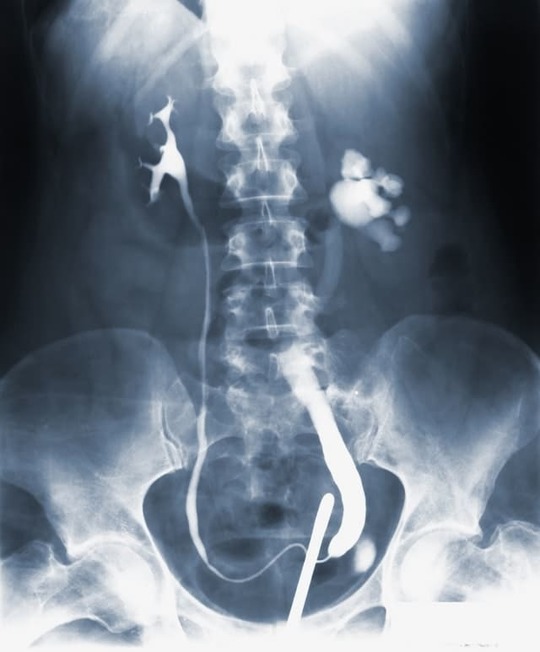

自己抗体である抗基底膜抗体を血液の中から取り除くために血漿を交換して改善を行うこともあります。腎機能の障害が進み、元に戻ることが難しい状態になってしまった場合には透析や腎移植が必要になることもあります。

グッドパスチャー症候群の改善の第一選択です。血液中にある 抗糸球体基底膜抗体を取り除き、肺出血や腎炎の進行を止めます。血漿交換を早期に行うことで、腎不全の進行を止める、または透析を回避できる可能性があります。

・腎不全、肺出血への対処方法

水分や塩分制限、血圧コントロール、電解質の管理を行います。腎機能が回復しない場合は人工透析の導入を行います。